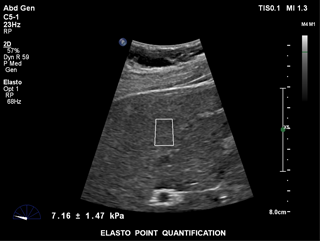

ElastPQ è un metodo facile da usare per ottenere i valori della rigidità dei tessuti epatici di una ROI predefinita. Utilizzando l'imaging in tempo reale come guida, la ROI viene posizionata sull'area di interesse e i dati relativi alla rigidità dei tessuti, ad esempio AVG, MEAN e IQR, vengono generati e visualizzati in pochi secondi. È possibile registrare più campioni e generare un referto sulle condizioni del tessuto epatico a partire dai risultati.